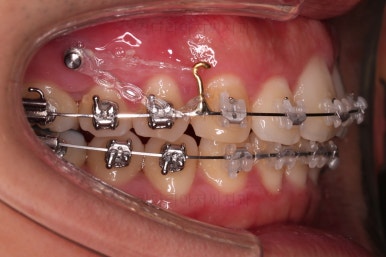

가지런하게 하고 틈새를 모으며 교합을 맞추기 위해서(위아래 치아가 서로 지그재그로 껴들어가게 하기 위해) 윗니들을 뒤로 뒤로 당겨줘요.

이 때 사용되는 장치가 미니스크류인데요.

다양한 위치와 방향으로 치아를 움직여줄 수 있답니다.